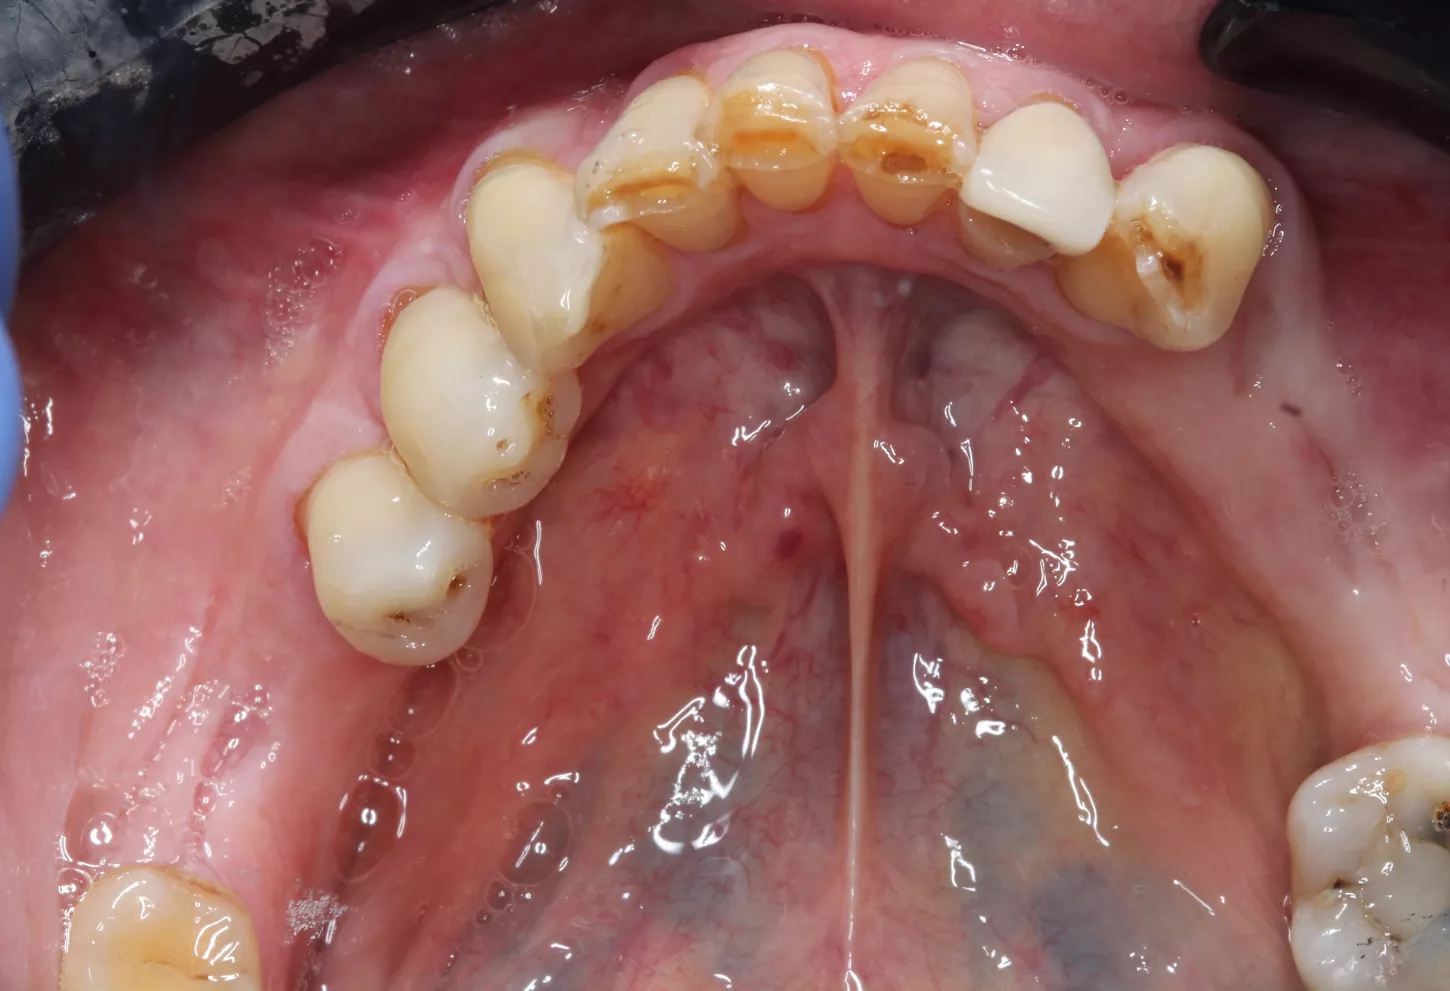

A 64-year-old male patient, in good general health, presented to our clinic with partial edentulism associated with compromised aesthetics, and impaired masticatory function. The patient expressed dissatisfaction with his smile and reported difficulty chewing due to multiple missing teeth.

Clinical and radiographic findings revealed missing teeth, failing prosthetic restorations, and chronic odontogenic infections, collectively contributing to functional impairment which negatively impacted the patient’s self-esteem and overall well-being, leading them to seek comprehensive implant-based rehabilitation. Given the patient’s clinical presentation and functional needs, a digitally driven rehabilitation pathway was selected to leverage the efficiency and predictability of current digital implant ecosystems. Contemporary digital workflows provide improved diagnostic accuracy, streamlined communication, and more predictable restorative outcomes compared with analogue approaches [1]. The integration of virtual planning, CAD/CAM‑guided surgery, and scannable anatomical healing abutments aligns with evidence demonstrating enhanced precision, reduced technique sensitivity, and better intraoral scanning fidelity in implant‑supported rehabilitation. Collectively, these advancements made the digital pathway the most seamless and biologically favourable treatment choice for this case [2].

• Periodontal stabilisation was first carried out to establish a healthy soft‑tissue environment prior to restorative and implant therapy. The esthetic rehabilitation plan included implant placement in sites LR6, LL5, LL6, and UL4, combined with porcelain veneers and crowns from UR3 to UL3 to harmonize the maxillary anterior smile.

• Edentulous sites were scheduled for implant-supported crowns. Axiom X3® Bone Level implants were selected based on their ability to achieve optimal primary stability and prosthetically driven positioning.

Initial situation

1. Panoramic view showing severe bone loss around tooth 15, confirming hopeless prognosis.